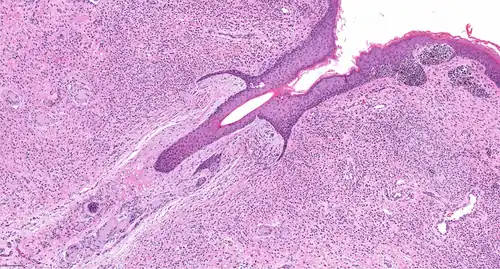

Naevuscellen zijn cellen van omstreden herkomst, óf afstammend van een stamcel uit de neurale lijst via naevoblasten, óf afstammend van een melanocyt. Het zijn in nesten liggende cellen met een grote celkern en veel cytoplasma met grove granulen (korrels).[1][2] Ze hebben geen dendrieten.

Ze bevinden zich meestal op de dermo-epidermale verbinding of in de dermis van de huid. Dermale naevuscellen kunnen verder worden onderverdeeld: type A (epithelioïde) dermale naevuscellen rijpen uit tot type B (lymfocytoïde) dermale naevuscellen, die vervolgens uitgroeien tot type C dermale naevuscellen, via een proces met neerwaartse celmigratie.[2] Daarna groeien ze nog verder uit in een dieper gelegen deel.[3]

Naevuscellen variëren in vorm, afhankelijk van hun locatie in de huid. Dieper liggende cellen vormen koord- of plaatvormige nesten.

- Type A. In de bovenste dermis en epidermis hebben de cellen pigment en zijn ze epitheelachtig met een kubusvormige of ovale vorm, een ronde of ovale celkern, iets kleiner dan die van aangrenzende keratinocyten en met goed gedefinieerde celgrenzen. Ze hebben overvloedig cytoplasma met grove melaninekorrels. Ze hebben fijn verdeeld chromatine en een fijn kernmembraan. Er zijn geen of kleine nucleoli.

- Type B. In de middelste dermis zijn naevuscellen niet gepigmenteerd, zijn ze kleiner en hebben ze een lymfocytachtig uiterlijk. Ze hebben minder cytoplasma dan type A cellen en geen melanine. De kernen zijn kleiner met verspreid chromatine en geen nucleoli.

- Type C. In de onderste dermis zijn ze spoelvormig met een ovale kern en lijken ze op fibroblasten of Schwanncellen.

- ‘Uitgegroeid’. Dieper gelegen deel van de moedervlek heeft kleinere cellen met minder pigment en zijn atypisch. Ze komen voor in kleinere nesten of als afzonderlijke cellen. Ze kunnen lijken op zenuwweefsel.[4][3]